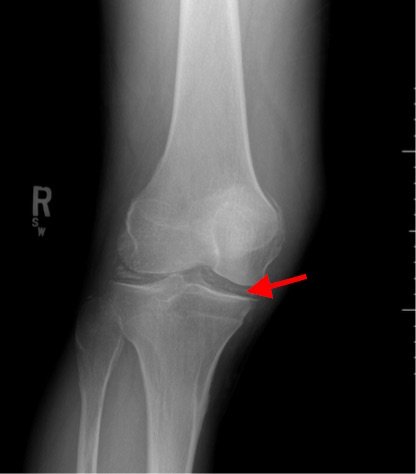

Radiographs of the knee showed multiple radio-dense lines paralleling the articular surface (see red arrows) consistent with calcium pyrophosphate crystal deposition within the joint often seen in calcium pyrophosphate disease (CPPD) also known as pseudogout.

Patients commonly present to the emergency department with non-traumatic joint pain. Arthrocentesis is an important diagnostic tool to evaluate for septic arthritis, gout, or pseudogout. Arthrocentesis can demonstrate crystals or abnormal cell count, gram stain, and culture.[1] In the evaluation of joint pain, plain films are usually obtained to evaluate for fracture, dislocation, effusion, or secondary signs of infection. In this case the classic x-ray supported the diagnosis of CPPD.2 The patient was found to have positively birefringent rhomboid shaped crystals consistent with pseudogout on arthrocentesis. Gram stain and culture were both negative. The patient was discharged with NSAIDs and had significant improvement in symptoms upon follow up with primary care physician in 3 days.